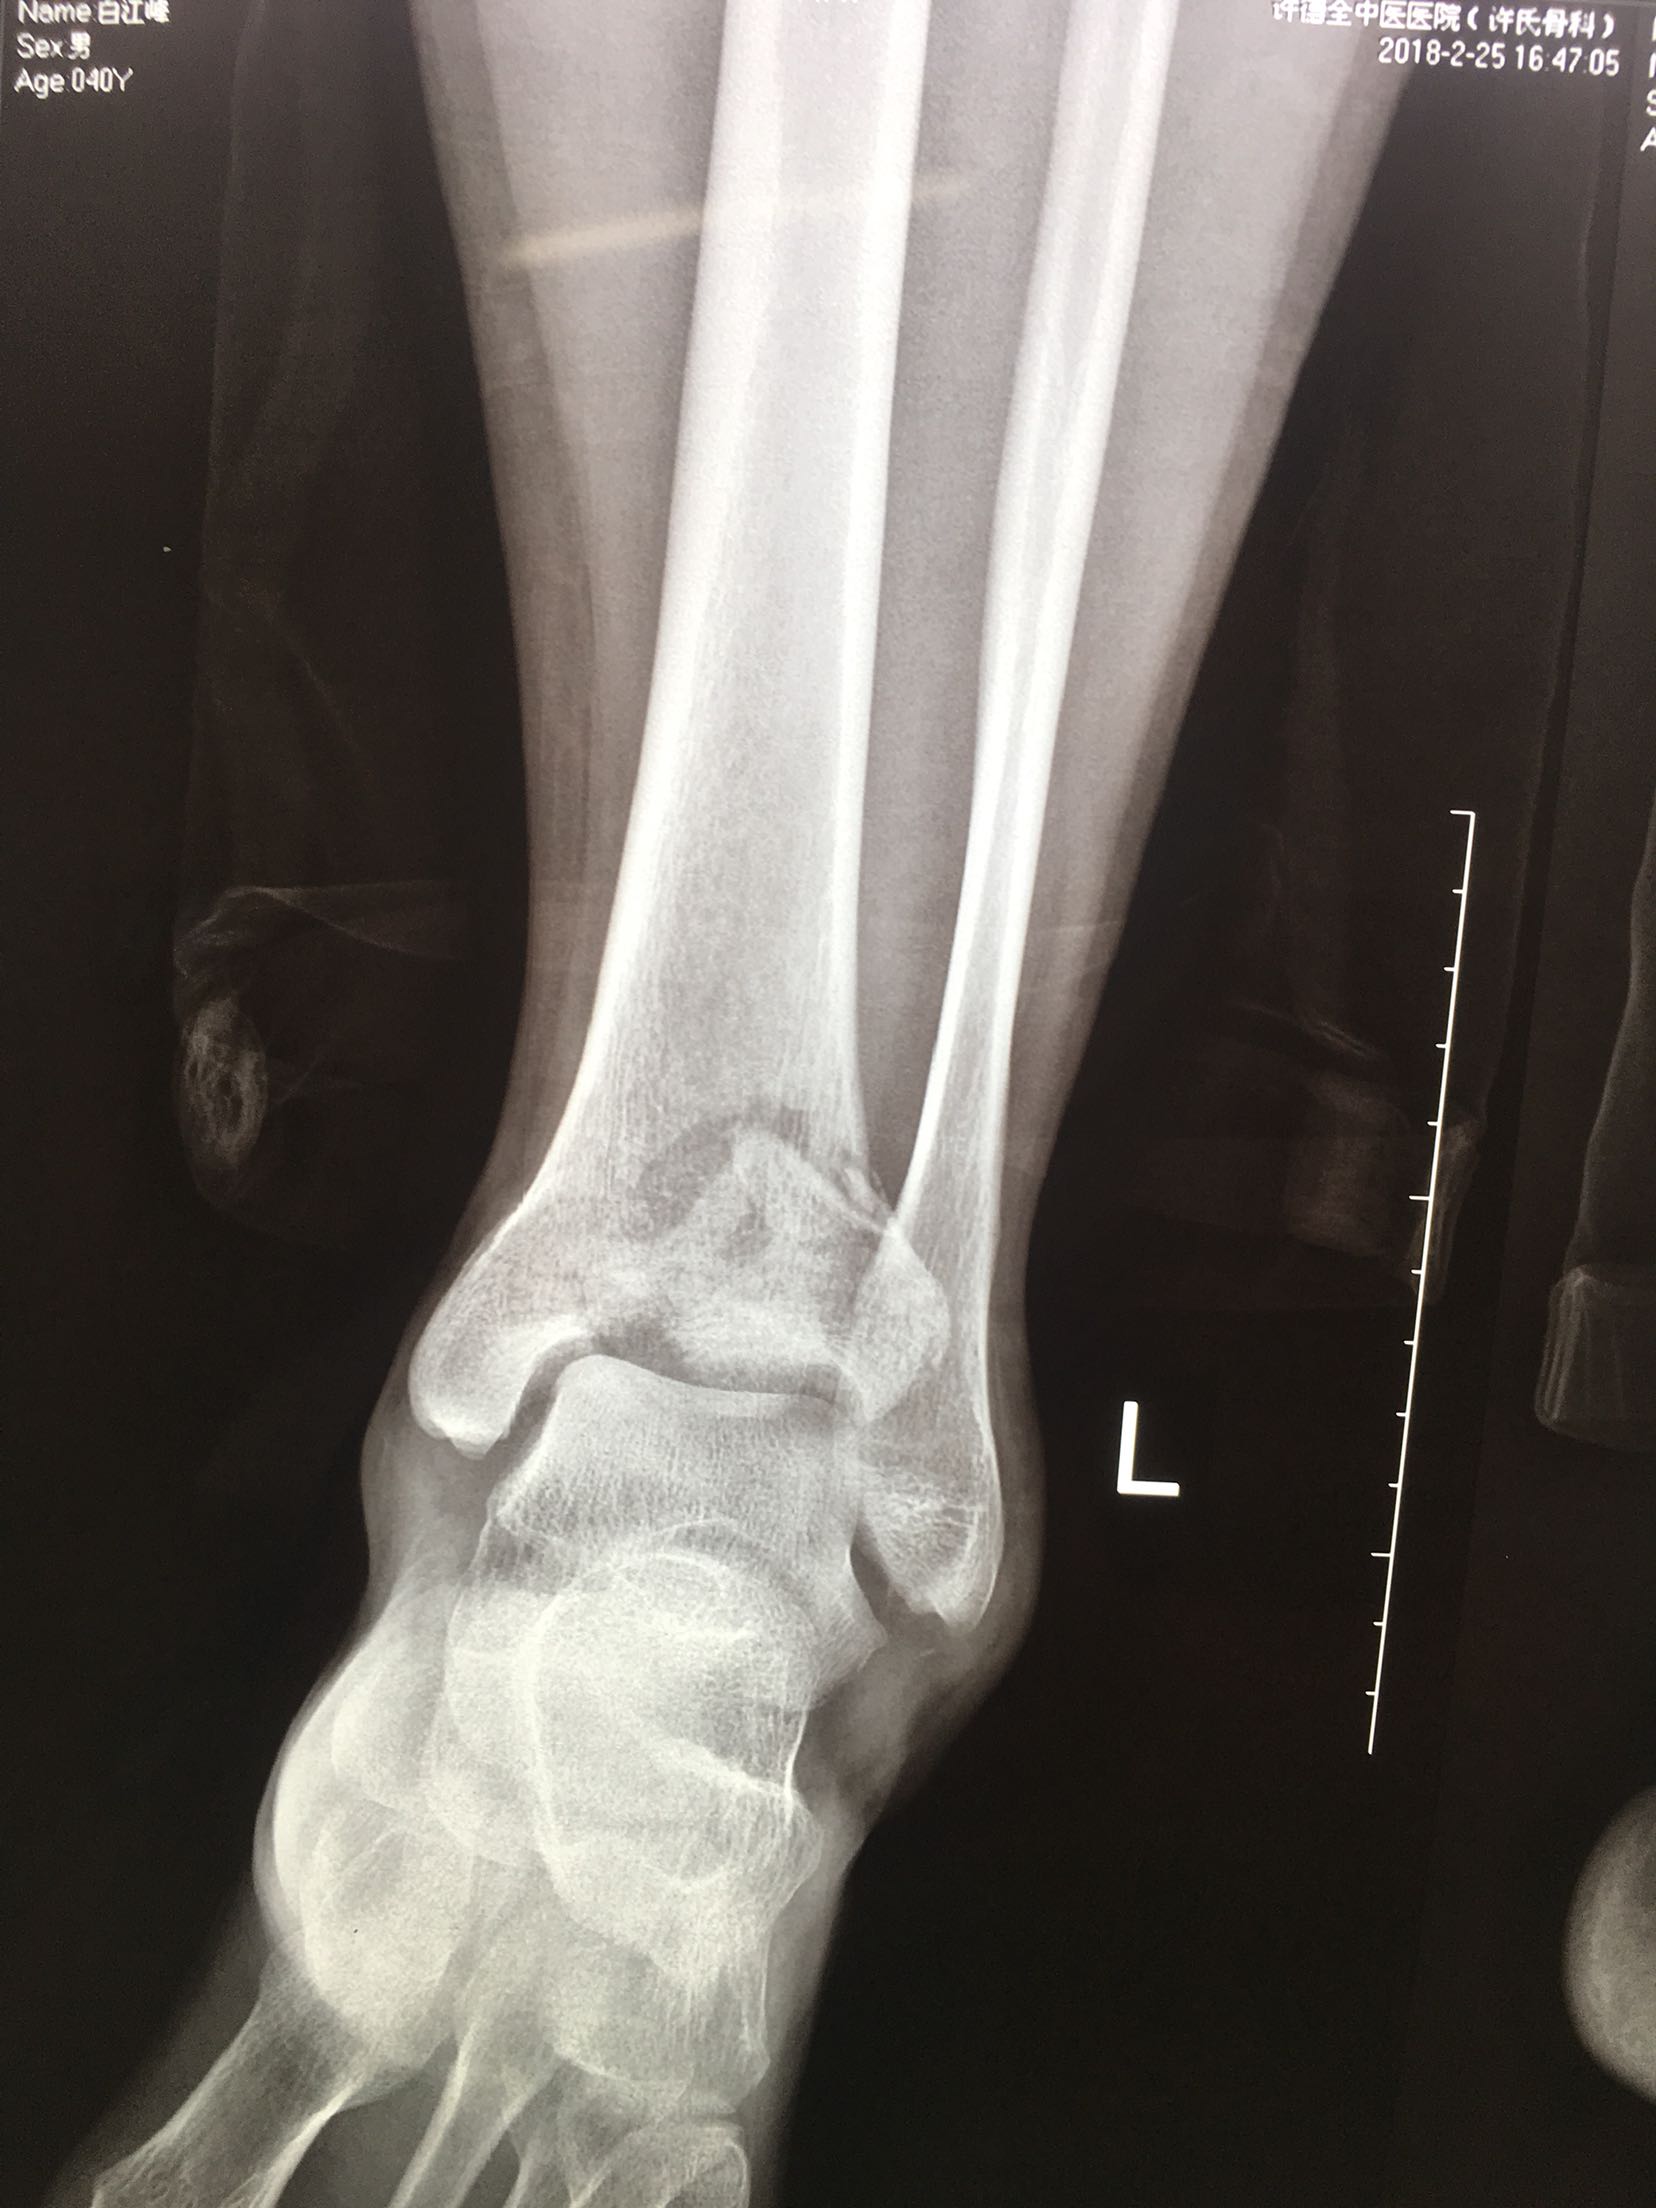

Pilon 骨折

患者,男性,41岁,坠落伤后左踝肿痛,活动受限1小时

左踝肿胀,局部皮色正常,皮温高,完整,无张力性水泡,畸形,踝关节活动受限,远端血运感觉正常。

完善检查,在腰麻下行切复内固定术,术后制动,消肿抗炎处理。